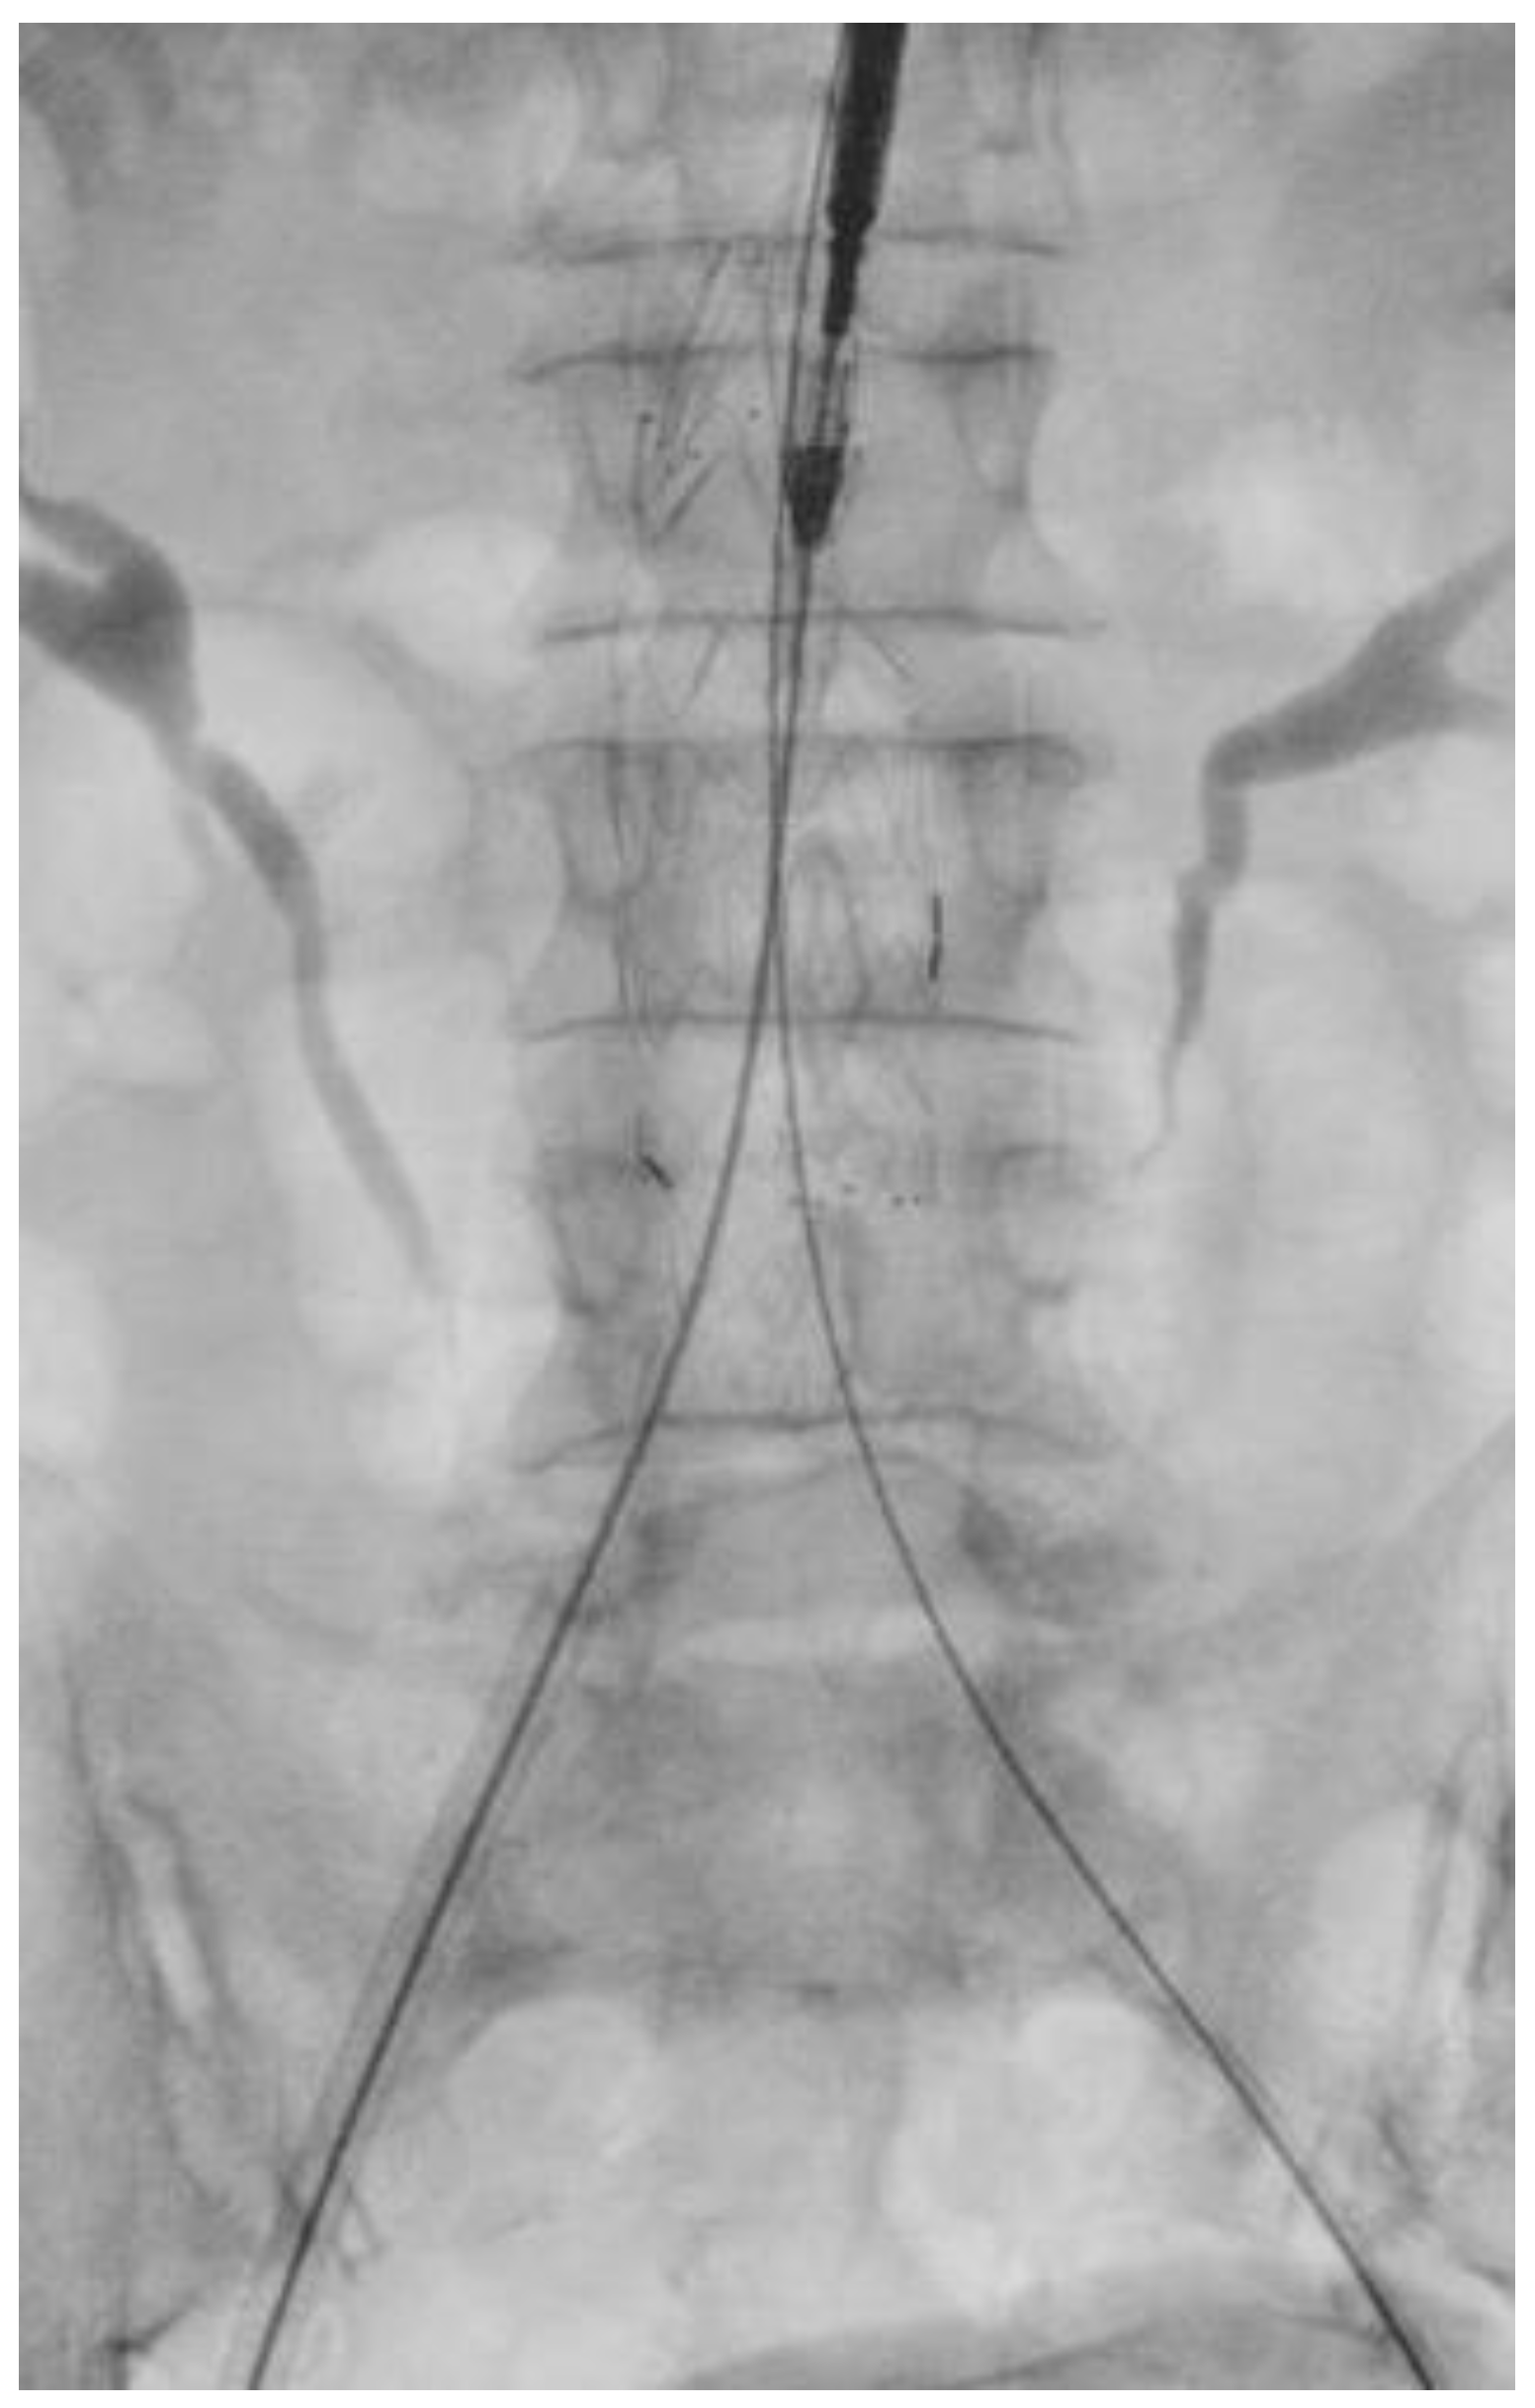

During the RGC procedure, the common femoral artery was surgically exposed and punctured with a Seldinger needle. A 6F sheath was then inserted. Afterward, a 0.035-inch Terumo floppy guidewire (Bolton Medical Inc., Sunrise, FL, USA) was advanced, followed by a 5F Cobra catheter (Bolton Medical Inc., Sunrise, FL, USA). The 0.035-inch guide wire was replaced with a Lunderquist extra stiff wire (Cookmedical Inc., Bloomington, IN, USA). A tail catheter was inserted through the contralateral access and advanced on the 0.035-inch guidewire. Once the 6F sheath was removed, the main body of the endograft was advanced and released. Cannulation of the contralateral gate was then performed using a 0.035-inch guidewire (as shown in Figure 1). The extra stiff guide was positioned, and the contralateral limb was deployed (as shown in Figure 2). The ipsilateral limb was then advanced and deployed, and finally, the femoral artery and wound were closed.

Figure 1.

Retrograde gate cannulation.